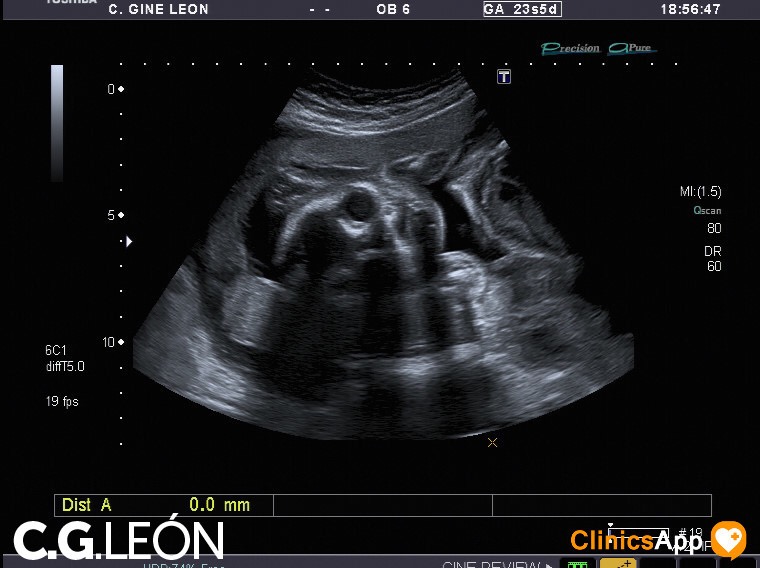

Aquí las fotos de la quinta ecografía, nada que destacar excepto que la ginecóloga estaba de mala leche y no se esmeró demasiado en las fotos. Hay una en la que se ve una mano, en directo se distinguía mejor, claro, porque se vio abierta como en la foto y luego la cerró. Pero por lo general encuentro de difícil interpretación este lote de fotos.